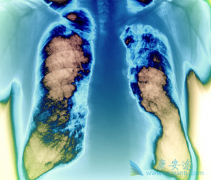

西达本胺联合埃克替尼在非小细胞肺癌中具有抗肿瘤活性

为了研究组蛋白去乙酰化酶抑制剂(HDACi) 西达本胺单独或联合表皮生长因子受体酪氨酸激酶抑制剂(EGFR-TKI)埃克替尼治疗 非小细胞肺癌 (NSCLC)的抗肿瘤疗效。研究人员开展了一项临床试验,研究了10个单用或联合使用西达本胺和埃克替尼的NSCLC细胞系的细胞 ...